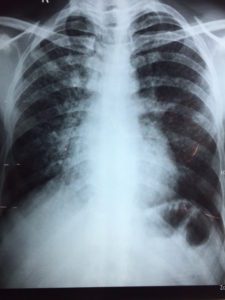

never waste your time with minor complaints; your knowledge and skills, however limited, can save lives (attached CXR reported as LVF: even my ex-consultant colleagues could do better – it’s miliary TB!); your willingness to help is openly appreciated; you learn about a new people, a new way of life, taste new and sometimes dubiously uncertain foods, and meet new friends; you see medicine you rarely see in the UK; and of course your view on life and medicine will never be the same.